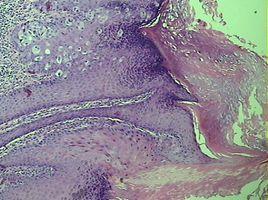

本病特點:①發病率低,好發於中老年人;②病史長,病情發展緩慢。其皮損為邊界清楚的紅色斑塊,表面伴滲出、結痂或脫屑,逐漸向周圍擴大,可發生潰瘍,多伴局部瘙癢。病理表現為病灶中存在特異的Paget’s細胞,該細胞單個散在或成簇狀,存在於上皮的基底層和深棘層內,亦可伸至上皮表層或毛囊鞘的外層以及汗腺導管和皮脂腺的上皮內。診斷主要依靠病變部位活檢病理學檢查。

派傑氏病起源於表皮原始幹細胞,也有作者認為起源於腺體。派傑氏病在國內較為罕見,但外陰屬於較易受累部位,與外陰癌相比,大約為53;1。該病好發於絕經後婦女, 主要症狀為頑固性外陰瘙癢和局部疼痛或燒灼感,典型病灶表現為外陰部隆起邊界清楚的紅色濕疹狀斑塊,有白色痂皮覆蓋,確診依靠病理活檢。鏡下見在表皮深層有派傑細胞: 細胞大、胞漿豐富、呈透明空泡狀。本病常同時並發其他內臟癌瘤,如前庭大腺癌、胃癌、乳腺癌等。